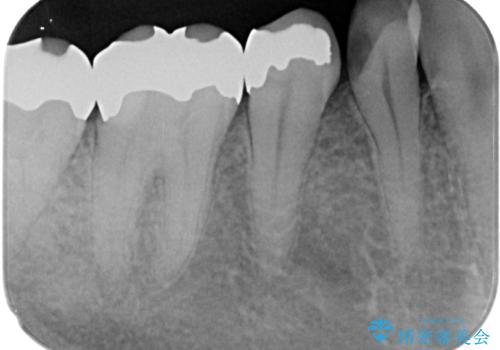

- 右下の銀歯が取れたとのことで来院された患者様です。以前にも取れていたところで、メタルインレーの不適合も認めていたため、次回外れたらオールセラミッククラウンにやり替えていくことを説明していたため、オールセラミッククラウンによる補綴治療を行っていくことにしました。

拡大鏡視野下で虫歯を除去しオールセラミッククラウンに適した形に整えました。